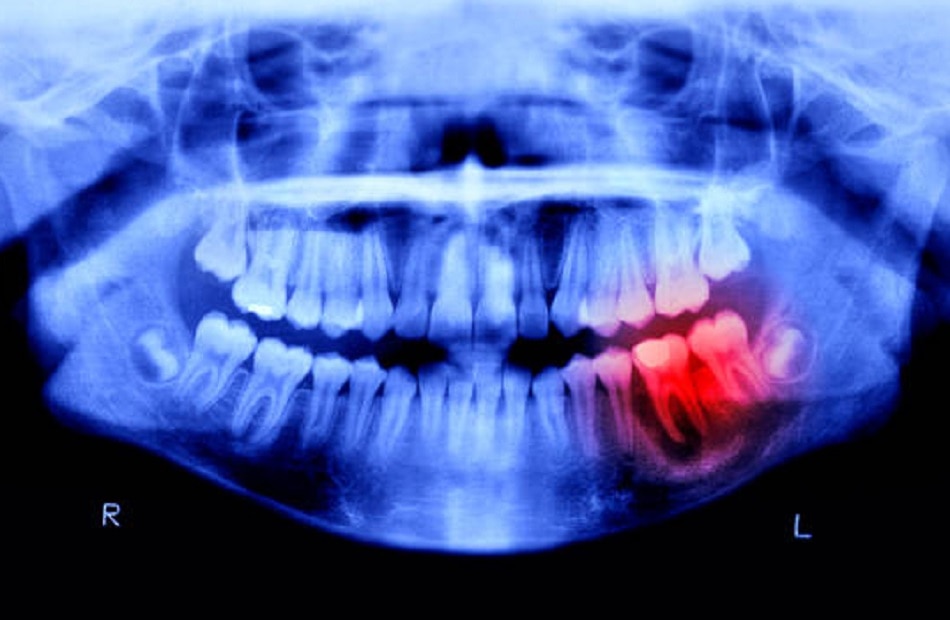

आड़े-टेढ़े दांत- जब किसी इंसान के जबड़ों में दांतों की लाइन सीधी ना हो तो उसकी होंठ काटने की आदत बढ़ सकती है. ऐसा तब होता है जब जबड़े के ऊपर और नीचे के दांत एक आकार के नहीं होते हैं या उनका आकार असामान्य होता है. अमूमन यह कोई बड़ी समस्या नहीं है, लेकिन जब आपको दर्द या होंठ काटने की समस्या हो या चबाने में मुश्किल होने लगे तो इसका जरूर इलाज कराना चाहिए.